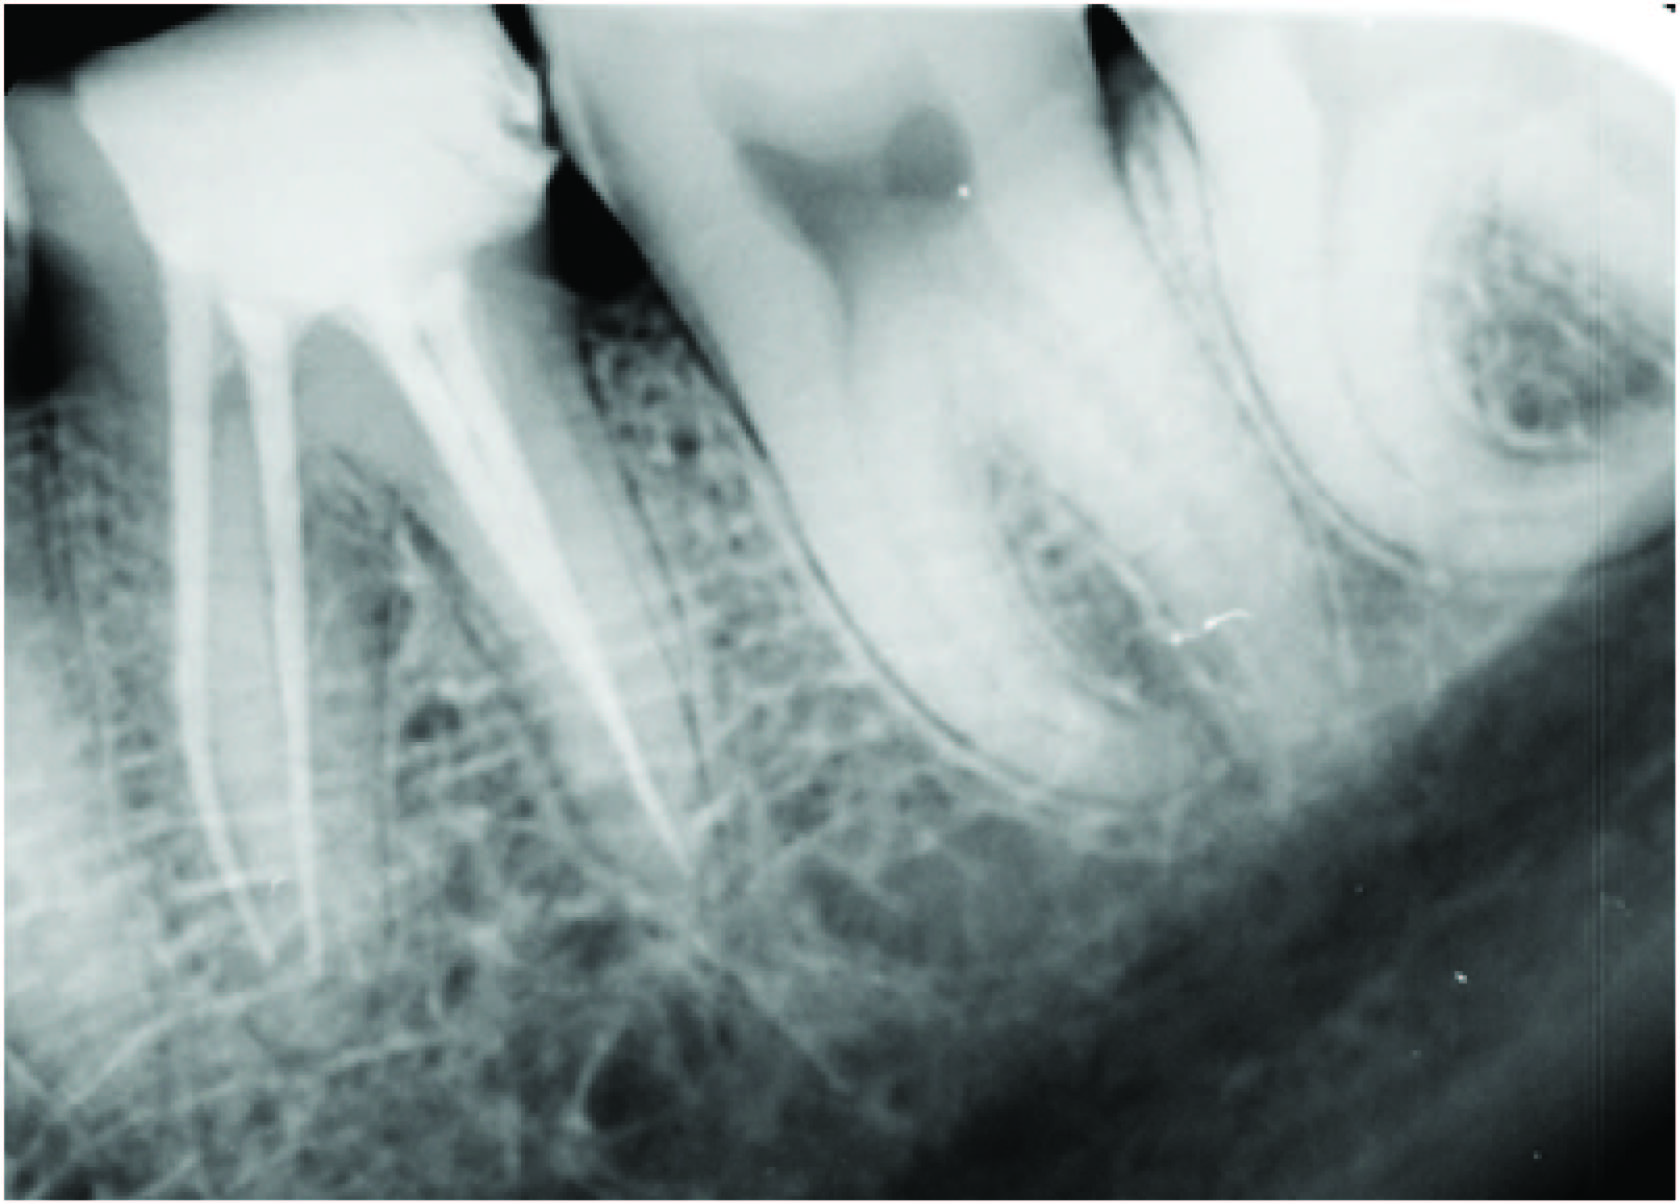

Intraoral periapical radiograph showing separated instrument

A 32-year-old male reported to department with chief complaint of pain in left lower back tooth region for last two days. Pain was sharp, severe and aggravated on taking hot and cold food stuffs. Patient was having disturbed sleep also. Clinical examination revealed carious lesion on distal aspect of mandibular left first molar. The tooth was sensitive to percussion also. A detailed radiographic examination revealed carious lesion on distal half approximating pulp and slightly widened periodontal ligament space around both roots [Table/Fig-1]. The tooth elicited positive response on electric and thermal pulp testing. Based on subjective and objective findings, a diagnosis of acute irreversible pulpitis was made and decision to do root canal treatment was taken. Root canal treatment was initiated under rubber dam isolation. Four canals were located and negotiated with size 8, 10 and 15 stainless steel K-file to their apices. Working length was determined using apex locator (Root ZX {J.morita,Tokyo,Japan}) with 15 K- file in all four canals. Cleaning and shaping was initiated with Rotary NiTi HERO Shapers under copious irrigation with 5.25% sodium hypochlorite and normal saline. During preparation of the distobuccal canal, approximately 10 mm of the size of 20, 0.04 taper HERO Shaper instrument fractured which was extending from the cervical third to the middle third of the root canal [Table/Fig-2]. A radiograph was taken to confirm the instrument separation [Table/Fig-3]. Following this event the patient was informed about the fractured instrument and the preparation of the rest of the canals were continued. Mesiolingual, mesiobuccal, distolingual canals were prepared with a size of 25, 0.04 taper HERO Shaper (MicroMega, Besancon, France). Prior to the filling of the canals, an attempt was made to retrieve the broken instrument from distobuccal canal with the help of the ultrasonic tip ET25 (satellac aceton, France). A radiograph was taken to confirm the instrument retrieval [Table/Fig-4]. On that attempt the instrument was removed successfully from the distobuccal canal [Table/Fig-5] and then was prepared till a size of 25, 0.04 taper HERO Shaper [Table/Fig-6]. All the four canals were then dried with paper points and obturated with gutta percha of a size 25 , 0.04 taper HERO Shaper and AH plus sealer (Dentsply Maillefer, Ballaigues, Switzerland) and a post obturation restoration was done with composite (SOLARE X GC corporation, Tokyo, Japan) [Table/Fig-7] . Follow up radiograph; after six months of treatment [Table/Fig-8] .